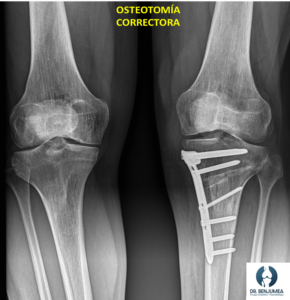

En casos severos o cuando el tratamiento conservador no es efectivo, puede ser necesaria la cirugía. Las técnicas quirúrgicas suelen incluir osteotomías de corrección, lo que quiere decir realizar un corte en el hueso para corregir la desalineación, actuando sobre la zona donde se encuentra la deformidad y colocando el hueso derecho. Para que se mantenga inicialmente esta corrección nos ayudaremos de dispositivos como placas, fijadores externos o clavos, que “sujetaran” el hueso hasta que este suelde.

Además, aplicaremos en ocasiones injertos de hueso, sustitutos óseos y células madre mesenquimales para ayudar en el proceso de cicatrización. La decisión de realizar una cirugía depende de varios factores, incluidos la edad del paciente, el grado de deformidad y la presencia de síntomas significativos.

La cirugía logra la corrección y consolidación ósea en la mayor parte de los casos, aunque hay que saber que el tiempo de recuperación completa es de varios meses. Sin embargo, en pacientes jóvenes es una opción adecuada para evitar la prótesis o retrasar la implantación de esta durante muchos años.